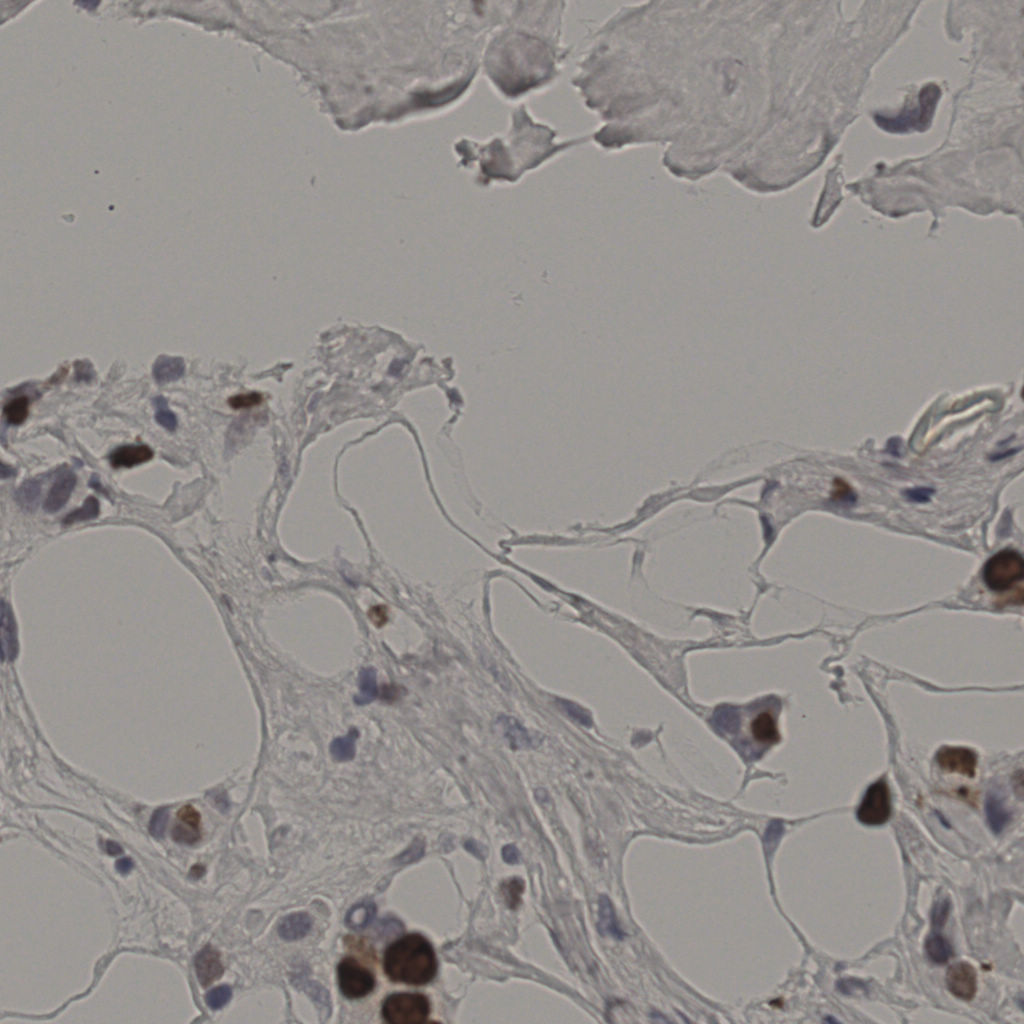

17.75%

Ki67 指数

阴 7986

阳 1723

切片统计

总切片

2640

有效

412

已标记

412

有效率

16%